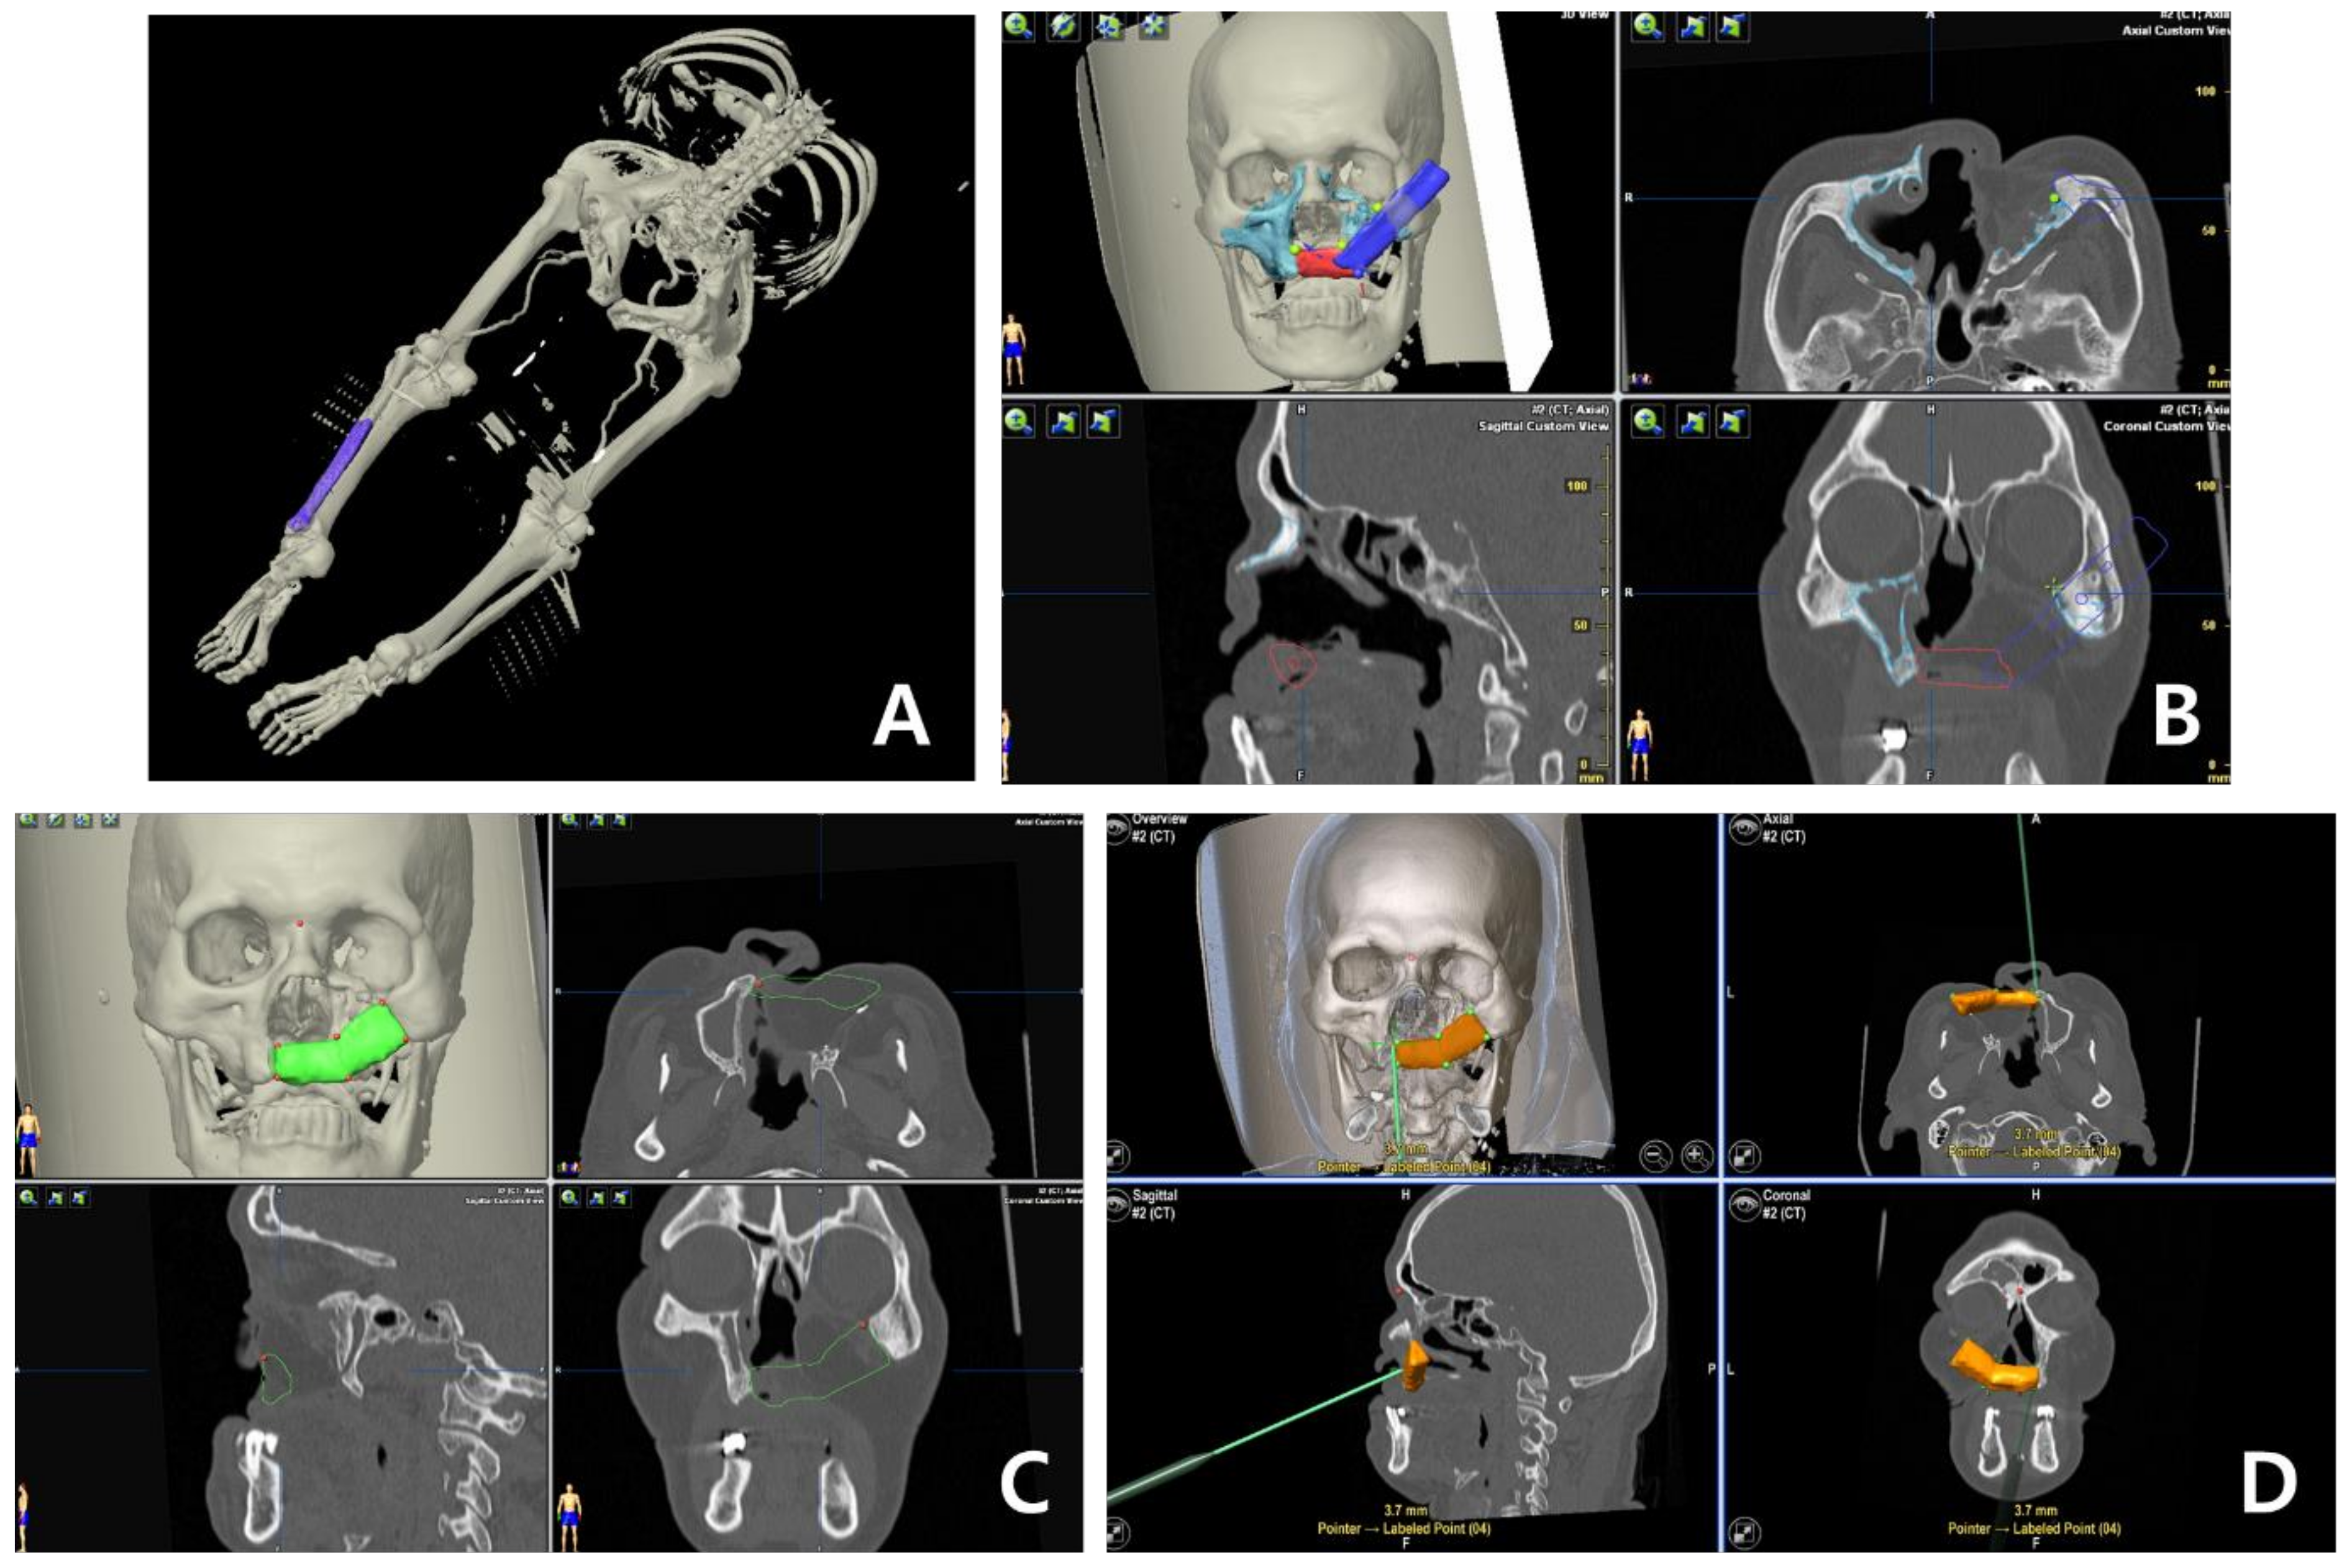

Delayed Reconstruction of Palatomaxillary Defect Using Fibula Free Flap

2. Materials and Methods

3. Results